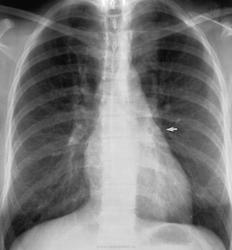

Особенностью рентгенологической картины при миксоме левого предсердия, если нарушения гемодинамики соответствуют митральному стенозу, является отсутствие выбухания ушка левого предсердия, полость левого предсердия расширена меньше, чем при митральном стенозе. При обызвествлении миксомы на рентгенограммах виден каль-циноз.